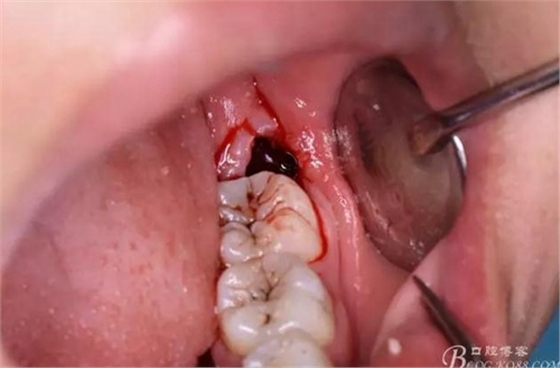

圖14.38牙根即將脫出牙槽窩

圖15.牙根脫位受阻,遂將牙根分為兩根